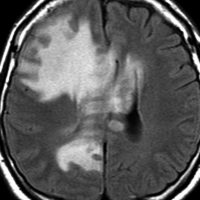

かなり広がった例でも治療ができる

かなり広範囲に急速に広がった例です。脳の他の悪性腫瘍,例えば膠芽腫や転移性脳腫瘍ですとこれだけ広がれば治る見込みがありません。でもリンパ腫は化学療法と放射線治療で治る見込みがある治療をすることができます。諦めないで急いで治療を開始してください。

60代女性で,皮膚結節がB cell lymphoma (neoplastic angioendotheliosis)がありました。1年後に急性の認知機能障害と歩行障害がありMRIで発見されたものです。SPECT, PET検査では多発性虚血性病変です。生検手術でIVLの診断が得られました。

左は発症時,右はCHOP化学療法1コース後のT2強調画像です。化学療法で寛解しました。